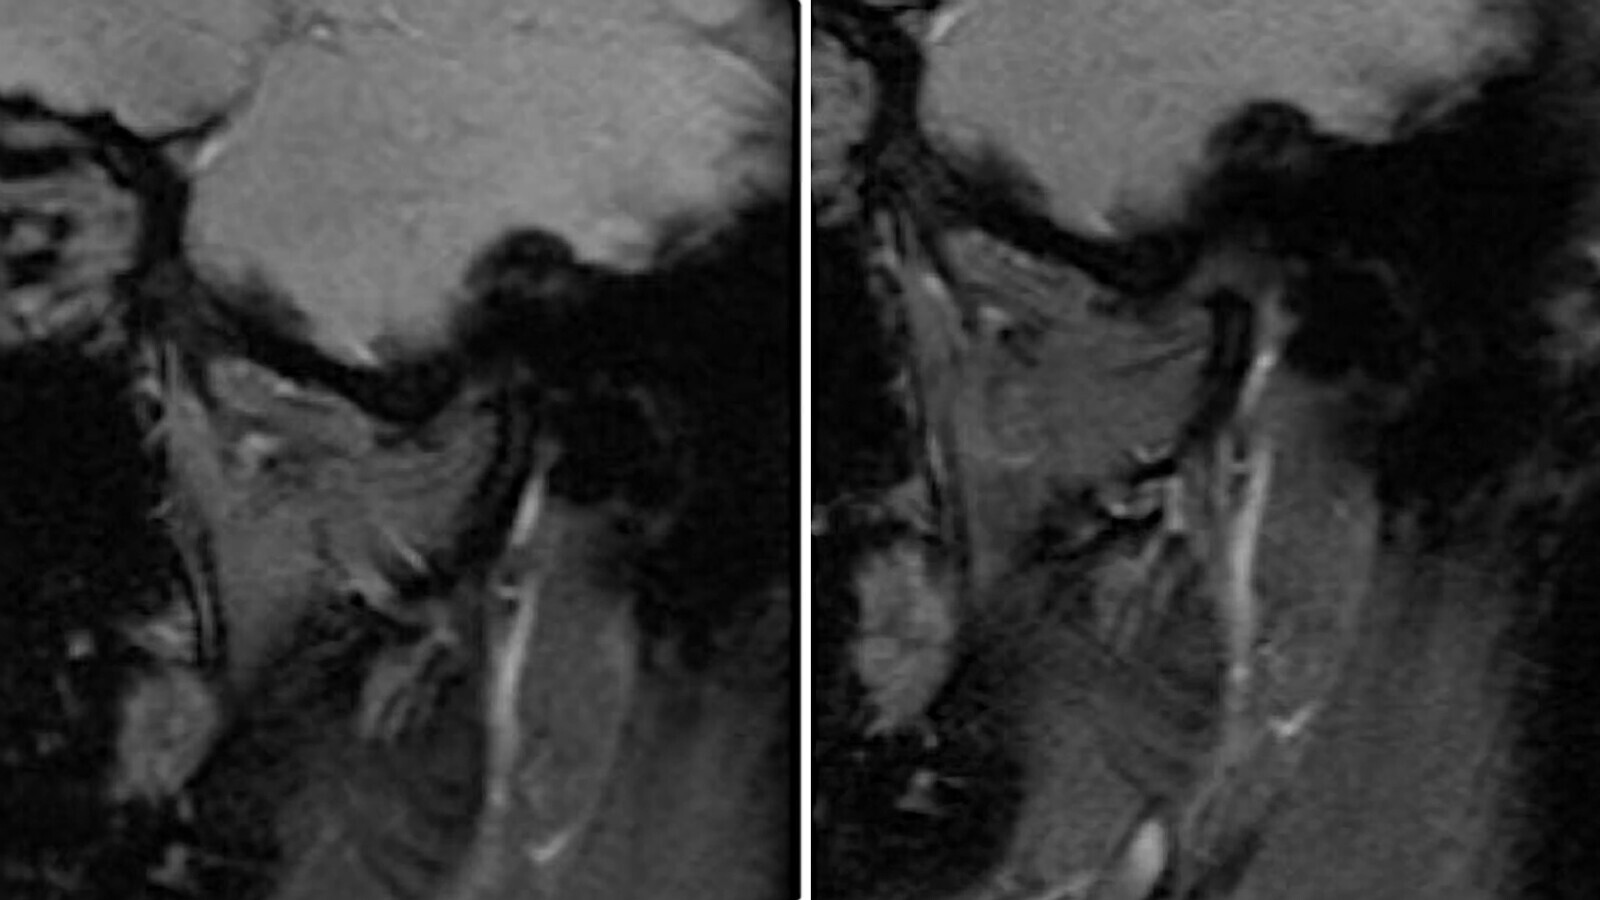

Figs. 1a-1b. Cortes sagitales de Resonancia Magnética de la ATM derecha, donde se puede observar la presencia de un Desplazamiento de Disco sin Reducción.